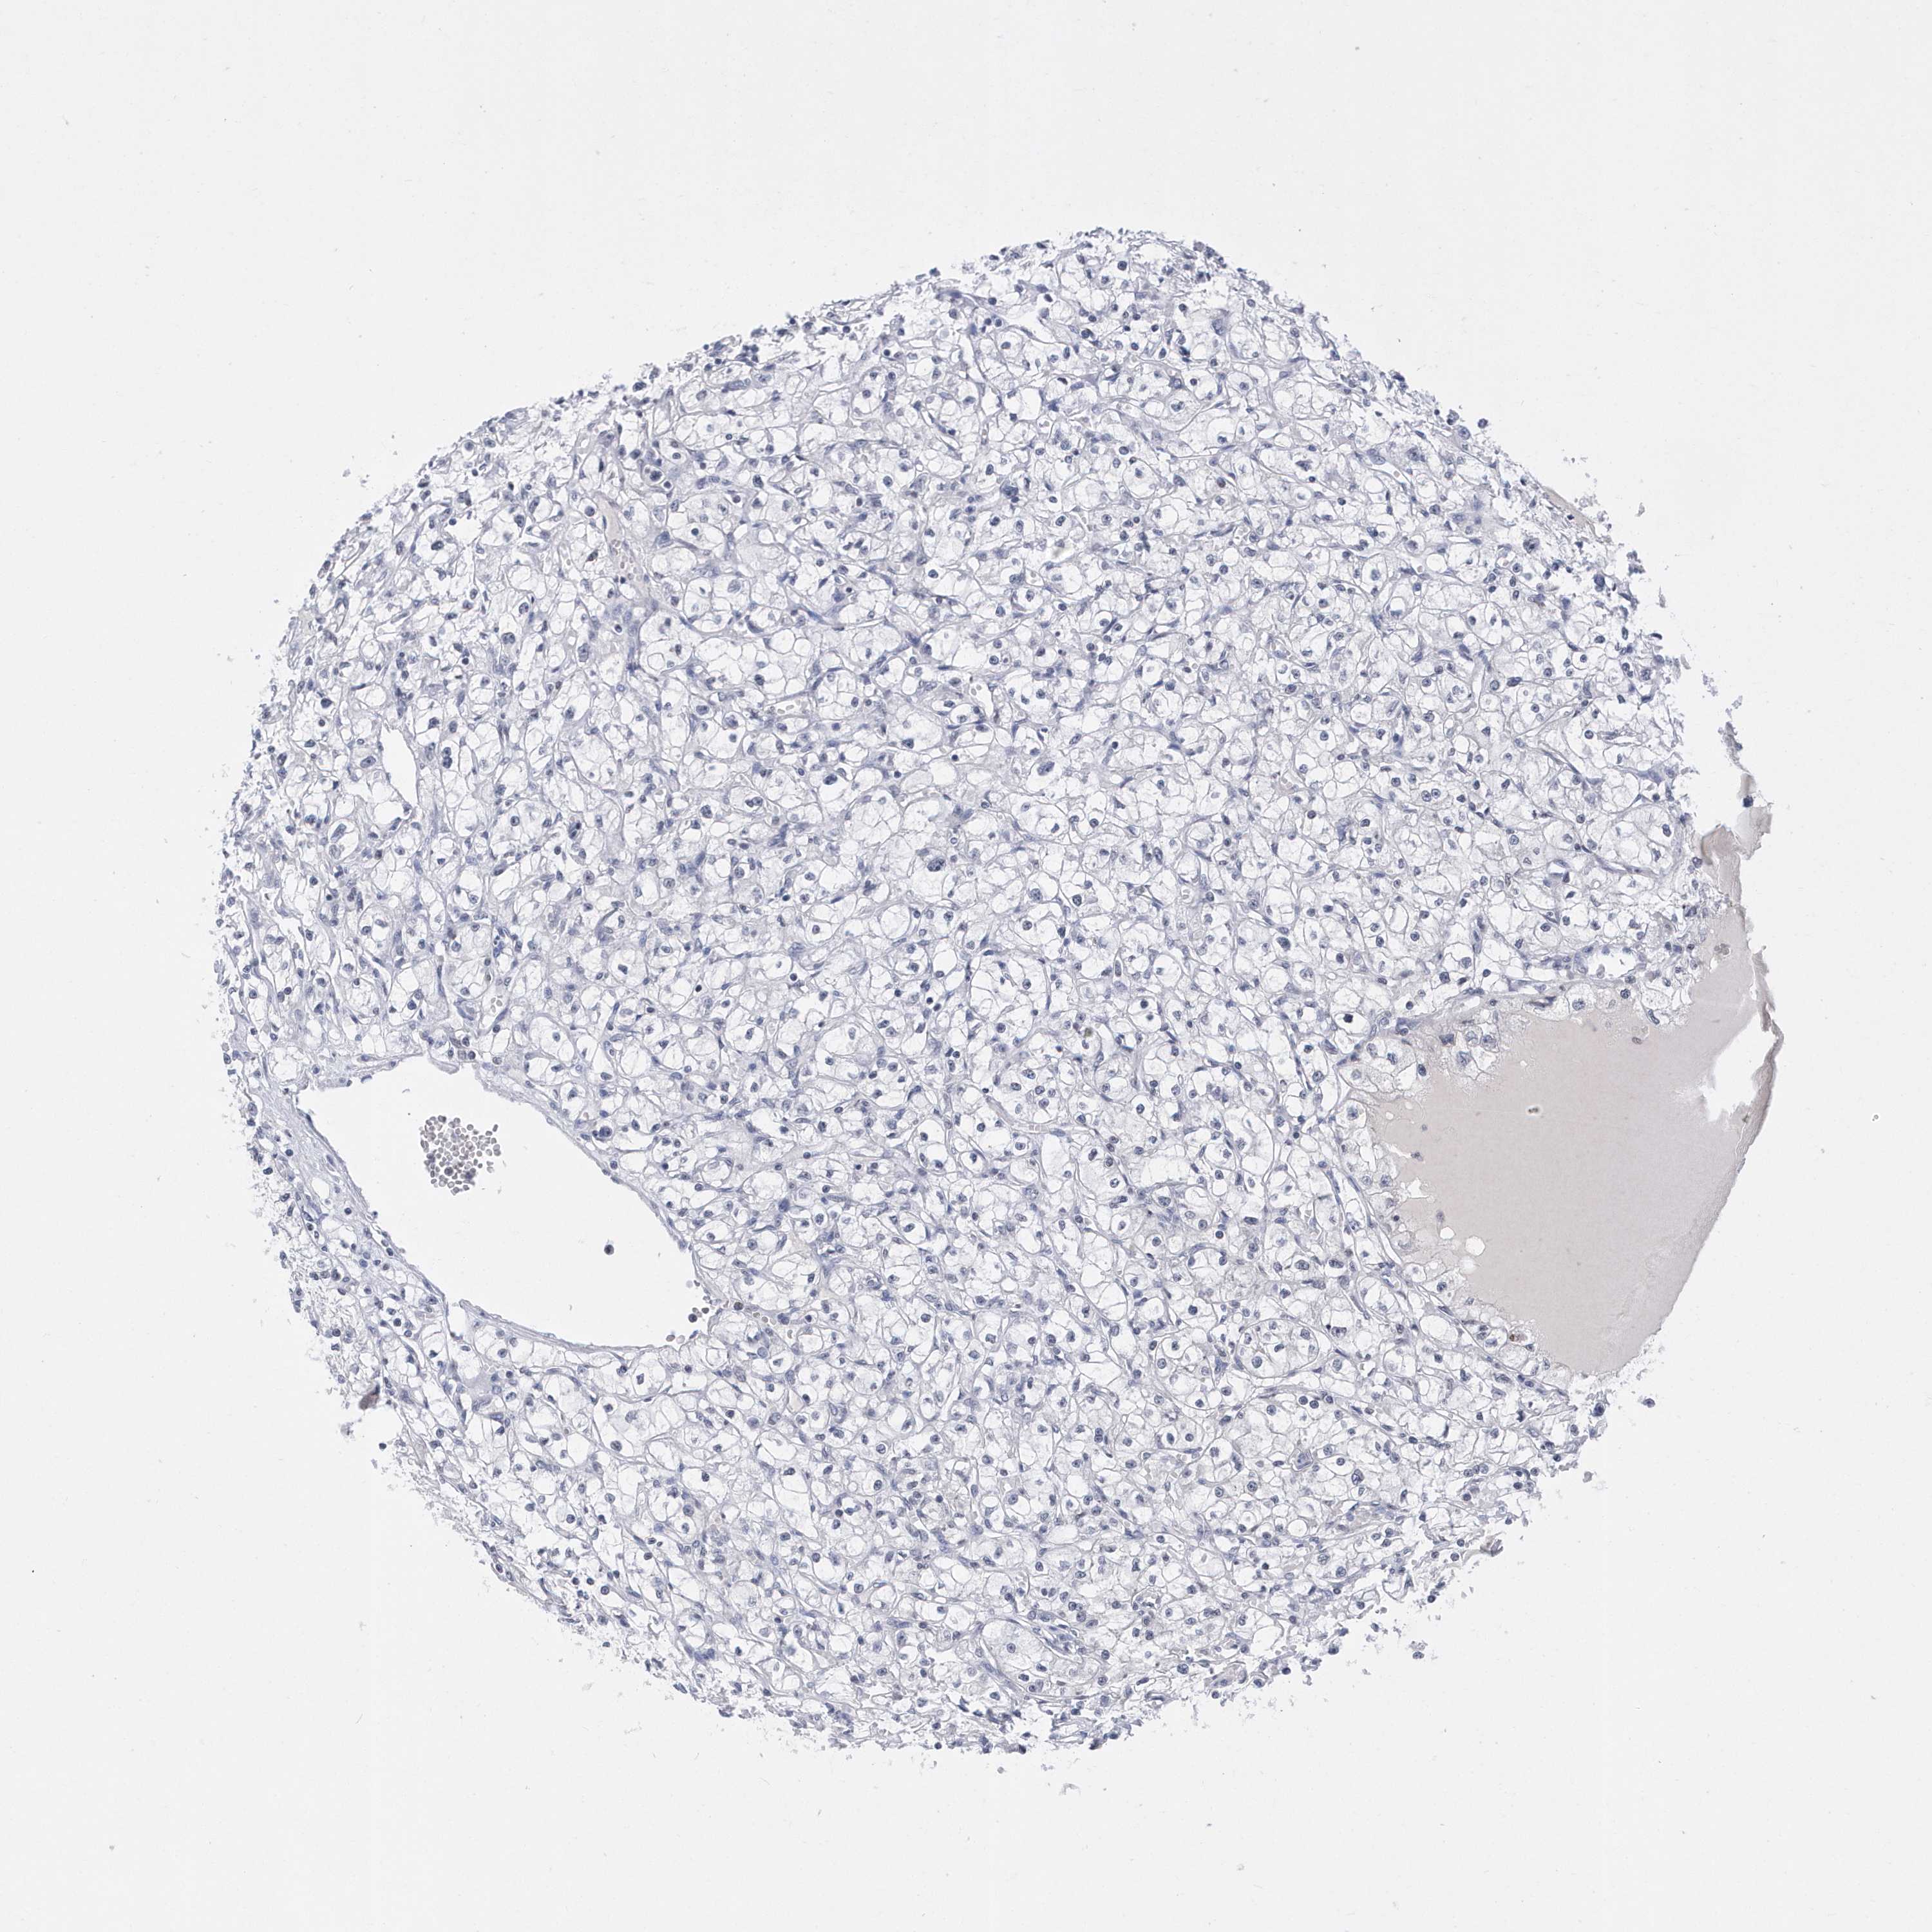

TCGA RNA samplesi

RNA-seq data is reported as average FPKM (number Fragments Per Kilobase of exon per Million reads), generated by the The Cancer Genome Atlas (TCGA) .

Normal distribution across the dataset is visualized with box plots, shown as median and 25th and 75th percentiles. Points are displayed as outliers if they are above or below 1.5 times the interquartile range. FPKM values of the individual samples are presented next to the box plot.

Average pTPM 0.1

Number of samples 100